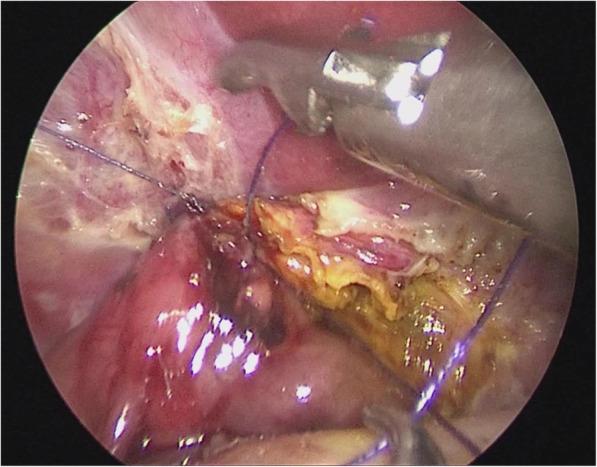

A modified technique of single-incision laparoscopic hepaticojejunostomy for children with choledochal cysts.

To present a modified laparoscopic surgical technique that works to optimize the surgical view in laparoscopic total excision of choledochal cyst in pediatric patients.

METHODS

From June 2015 to June 2017, a total of 48 pediatric cases of choledochal cyst were admitted. Their age ranged from 15 month to 8 years (average 3.5 years). The Todani types were: type I (n = 32) and type IVa (n = 16), according to the diagnostic criteria of ultrasound, abdominal computed tomography (CT) and magnetic resonance cholangiopancreatography (MRCP).

RESULTS

Total cystic excision with hepaticoenterostomy was accomplished laparoscopically in 48 cases with our transumbilical single -incision method without conversion to open surgery. Average duration of operation was 200 min (range 170-240 min), average intraoperative blood loss was 9 ml (range 6-14 ml) without the need for blood transfusion. The 72-h postoperative ultrasound reported no abdominal effusion, when the intraperitoneal drainage tube was removed. There was no postoperative complication during the 6 months of follow-up.

CONCLUSIONS

We accomplished the same postoperative outcome in laparoscopic total cyst excision with our modified method as that with conventional laparoscopic surgery. This technique allows the operator to have a stabilized surgical view without needing to rely on an assistant to hold up the liver lobe for larger operative space.